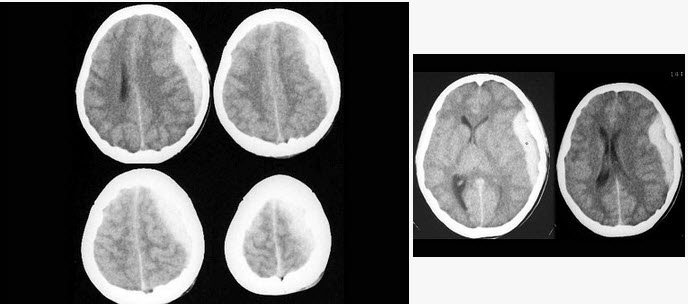

50、单项选择题

女,37岁,产后10天,出现剧烈头痛头昏伴神志不清2天,根据所提供图像,最可能的诊断是()

A.右侧蛛网膜下腔出血

B.右侧脑膜脑炎

C.右侧硬膜下血肿

D.右侧脑梗死

E.右侧静脉窦血栓形成